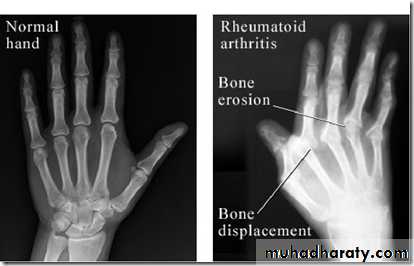

Radiological findings

Radiographic changes typical of RA

Synovitis = feels like doughy - Spindyling of the fingers- Wrist expansion - Hand deformities (boutonniere and Swan-neck)

- Boutonniere = hyperextension DIP, flexion of PIP- Swan-neck = hyperflexion DIP, extension of PIP